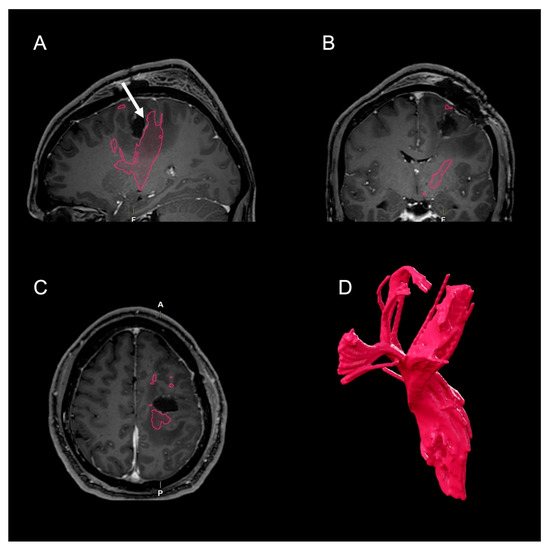

2. Case Presentation